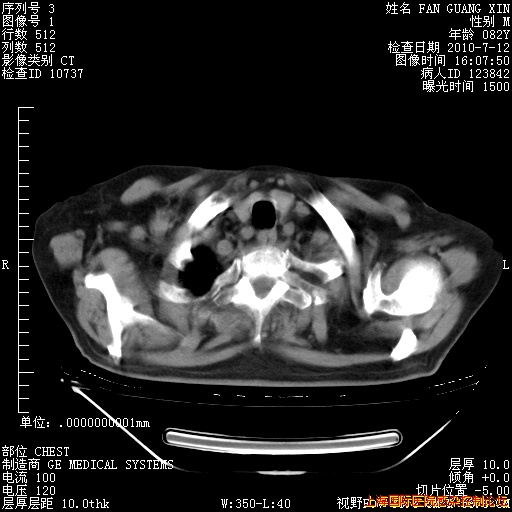

6月12日纵膈窗